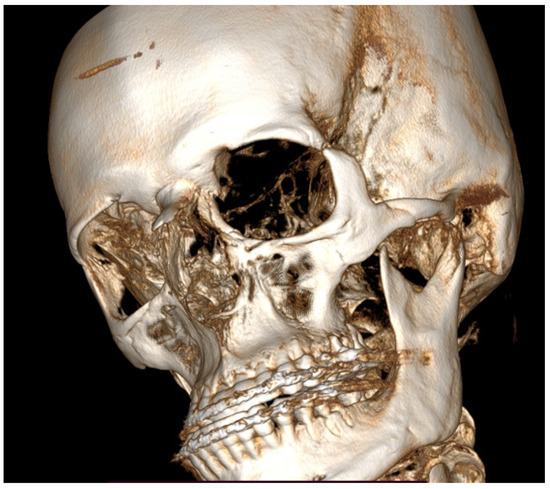

Figure 5.

A CBCT-3D reconstruction with visible enlargement and overgrowth of the left mandibular condyle head. Also, a tendency for skeletal class III deformity is visible. In such cases of severe skeletal asymmetries, a necessity for orthognathic surgery procedures is quite important to improve facial symmetry, oval, and contour. The presented images are quite interesting because the unilateral condylar hyperplasia in this case slowly grew over the years and was not found before the first orthognathic procedure in the past; this was the main source of skeletal asymmetry relapse over the next years.